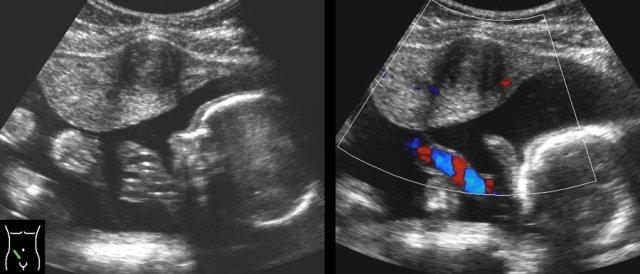

Nang tồn lưu hoặc nang xuất huyết.

Ở phụ nữ trẻ có đau bụng cấp tính, hình ảnh phần phụ dạng nang to ra, có hoặc không kèm theo dịch tự do, là một phát hiện thường gặp.

Trong hầu hết các trường hợp, đây là nang chức năng đã vỡ hoặc đang chảy máu.

Các xét nghiệm thường trong giới hạn bình thường với CRP thấp và các bất thường trên siêu âm sẽ biến mất trong vài ngày hoặc vài tuần.

Ca lâm sàng 1

Ở người phụ nữ trẻ này, phát hiện một khối lớn dạng nang một phần với thành phần đặc, không có mạch máu (cục máu đông).

CRP duy trì ở mức thấp và cơn đau biến mất sau hai ngày.

Siêu âm theo dõi sau 6 tuần cho thấy hình ảnh hoàn toàn bình thường.

Cần lưu ý rằng các hình ảnh siêu âm này cũng có thể hoàn toàn không có triệu chứng.

Ca lâm sàng 5

Các nang xuất huyết tồn lưu thường chứa các khối đặc, không có mạch máu, không đồng nhất, đại diện cho cục máu đông.

Sự co rút của các cục máu đông này thường tạo ra các bờ lõm (đầu mũi tên).